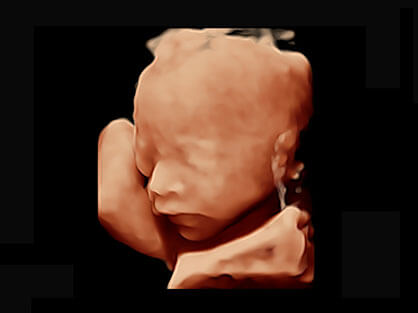

作为P系列家族成员之一,P40 Plus采用狗万官方网站高端超声系统平台——极光,并以时尚秀丽、小巧灵动的外观设计绽放出灵动之韵、科技之美。高端平台的使用保证了P40 Plus优质的基础图像;完备的高级功能可满足您全身应用的基本需求;丰富的探头配置、多样的高级4D成像及分析软件为您日益增多的妇产应用需求提供丰富的诊疗方案。

可同时显示组织结构表面和内部的轮廓信息,达到透视效果,为临床提供更丰富的诊断信息。

宽频带腹部凸阵探头和腹部容积探头、大角度腔内探头和腔内容积探头、独特的生殖专用曲柄探头,为妇产应用提供全面诊疗方案。

大角度腔内容积探头,可完整包络子宫及盆底结构,充分展示组织结构毗邻关系。